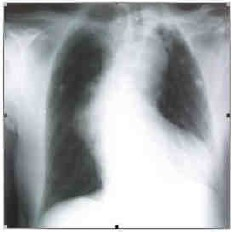

Paciente de 68 anos, do sexo masculino, com história de hipertensão, apresentou-se na Emergência com quadro de síncope ocorrida havia duas horas. Ao chegar à Emergência, estava acordado, ansioso, pálido e com PA 100/60mmHg. O eletrocardiograma (Fig. A) e o Rx de tórax (Fig. B) estão representados abaixo.

Fig. A

Fig. B

Com relação ao caso relatado acima, a melhor abordagem a seguir é